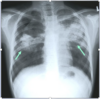

87

What are the four arrows pointing at?

* Cavitary Infiltrate